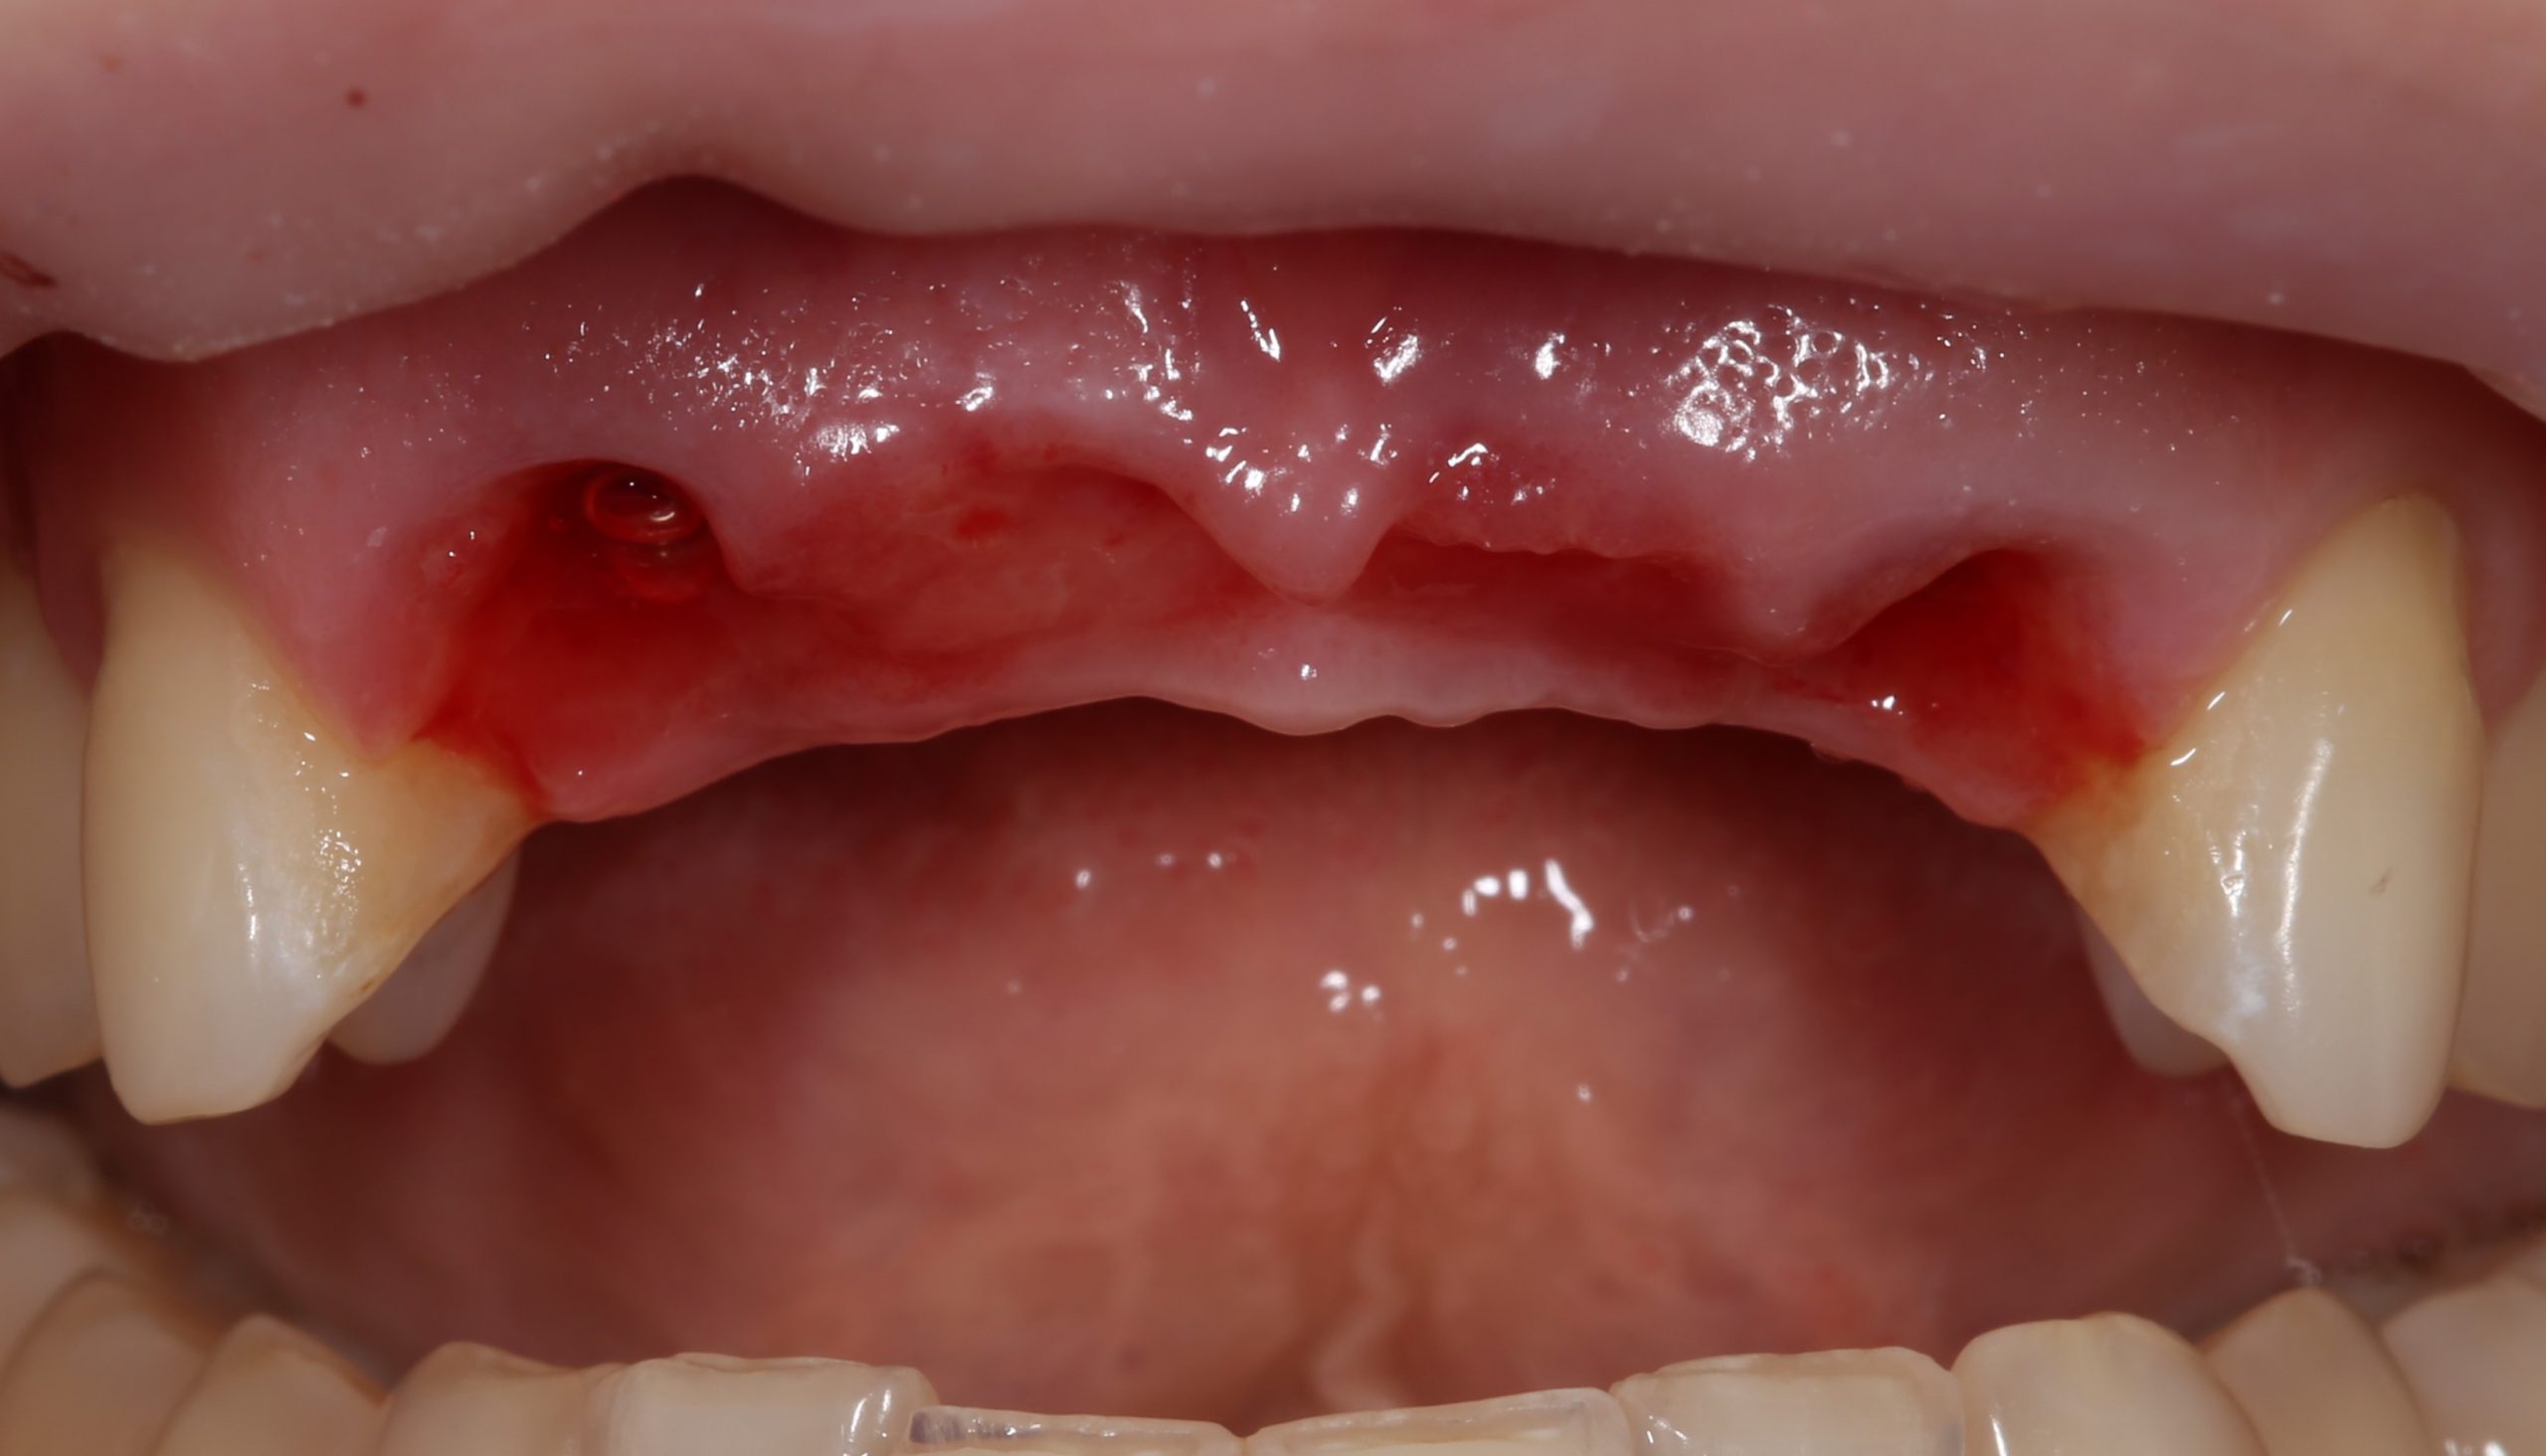

Вместо реплантаций (что легко) и реставраций (что сложнее), её тогдашний стоматолог решил решил депульпировать и обточить два боковых резца и сделать мостовидный протез. С тех пор прошло много времени, протез несколько раз меняли, а зубы перелечивали. На момент обращения к нам, верхние резцы у Татьяны выглядели следующим образом:

Пациентку беспокоили дискомфорт в области протеза, небольшая подвижность и периодическое воспаление десны в области опорных зубов.

За день до операции Давид снимает мостовидный протез:

и еще раз убеждается в том, что мы приняли правильное решение заменить опорные зубы на имплантаты:

И действительно, даже при условии качественного лечения корневых каналов, то, что осталось от боковых резцов, вряд ли можно нормально протезировать.